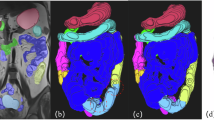

First, the observer marked the intestinal tracts, which sequentially appeared in all the 35 MRIs, and then visually selected a set of corresponding intestinal tracts from each of the 35 MRI images. The process of extracting a two-dimensional feature vector from the intestinal tract of interest for a patient with CIPO in MRI images is shown in Fig. 3. The intestinal tract of interest was represented as a two-dimensional feature vector and plotted on the two-dimensional feature space. We examined 78 intestinal tracts of interest from 18 samples. For each of the intestinal tracts of interest, 35 luminal diameters were separately measured. The total number of luminal diameters measured, which were used to calculate the J values and Mahalanobis distance, was 2730. With this method, it is important to consider inter-observer variability, because the variability is mainly produced by the observer. Hence, each luminal diameter was independently measured by two observers. Next, we checked the differences in the measurements performed by both observers and repeated the luminal diameter measurement in cases where a large difference was observed. The mean \(m\) of the 35 luminal diameters was estimated. Similarly, the means from each of the healthy volunteers and the mean \(\mu\) and variance \({\sigma }^{2}\) of the resulting means were also estimated. Next, the Mahalanobis distance was calculated, and its logarithm was obtained as the first feature x1. On the other hand, J values were calculated from luminal diameters, and the 34-dimensional motility vector was generated using J values. Then, the distance between the two vectors was adopted as the second feature, i.e., distance variation per time x2. The method is described in detail below.

where μ and σ2 are the sample mean and sample variance of the volunteer distribution, respectively. The sample mean and sample variance were estimated using the means for each of the intestinal tracts of healthy volunteers. Then, we calculated the logarithm of the Mahalanobis distance D(m); thus, any intestinal tract was represented as a two-dimensional vector whose components x1 and x2 were the logarithm of the Mahalanobis distance and distance variation per time, respectively. These x1 and x2 are new cine MRI parameters. In pattern recognition, the parameters x1 and x2 are called features. Each intestinal tract was represented as a feature vector in a two-dimensional feature space.